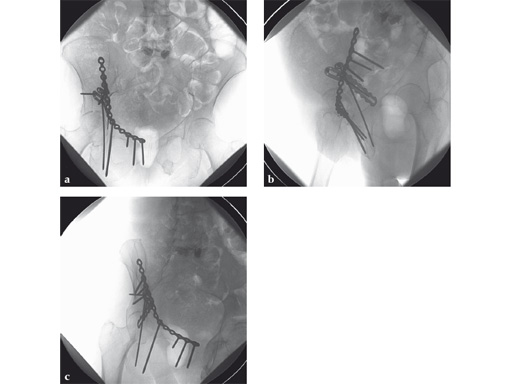

Fig 4ac AP pelvis and Judet oblique x-rays 9 months postoperatively. The patient started full weight bearing at approximately 10 weeks postoperatively. The fractures healed without secondary displacement. The patient returned to preinjury (relatively limited) activity level with no significant residual pain complaints.

Note: In this case the quadrilateral surface plate has been useful both as an interim reduction aid and to augment prior stabilization constructs. In effect, it provides a "prosthetic" cortex for the quadrilateral surface as well as enhancing posterior column stability in a way not possible with typical anterior to posterior column lag or position screws alone.